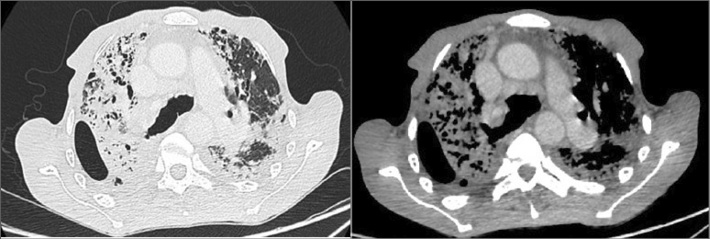

Mujer de 39 años con exposición a humo de biomasa durante 3 años, sin antecedentes de tabaquismo, nuemotóxicos, tuberculosis, ni enfermedades autoinmunes. Presentó dolor torácico, disnea y pérdida de peso de 4 años de evolución. Fue inicialmente diagnosticada con secuelas de tuberculosis. (Figura 5) Una nueva TC evidenció opacidades fibro-retráctiles pleuropulmonares, disminución volumétrica de lóbulos superiores, distorsión arquitectural con progresión hacia lóbulos inferiores y marcada depresión en horquilla supraesternal. (Figura 6) Patrón restrictivo muy severo (CVF 23%), difusión de monóxido de carbono (DLCO), descenso severo 25%. Biopsia pleural, pericárdica y pulmonar mostraron: neumonitis intersticial-septal con predominio de fibrosis, sin patrón de neumonía intersticial usual, ni granulomas ni microorganismos; además pleuritis y pericarditis crónicas inespecíficas.

Caso 2. TC de tórax inicial. Engrosamientos pleurales apicales, disminución volumétrica de lóbulos superiores, consolidaciones pulmonares fibro-retráctiles, con distorsión de arquitectura pulmonar y extensión a lóbulos inferiores. Marcada depresión en la horquilla supraesternal.

Caso 2. TC de Tórax en evolución. Progresión del compromiso fibro-retráctil del parénquima pulmonar, a predominio de lóbulos superiores.